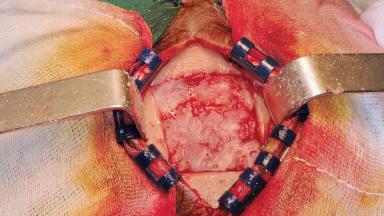

Iliac and Calvarial Bone Blocks for Onlay Grafting of a Severely Resorbed Edentulous Maxilla

A 45-year-old woman with a completely edentulous maxilla was referred to evaluate the possibility of rehabilitation with an implant-supported prosthesis. This patient was healthy and a non-smoker. She had been wearing a maxillary complete denture opposing a natural mandibular dentition since her twenties. This situation had resulted in progressive resorption of the alveolar ridge, repeatedly creating a need for relining the denture. Twenty years later, despite multiple adaptations and the use of “glues” the denture was unstable and causing the patient psychological and functional discomfort.